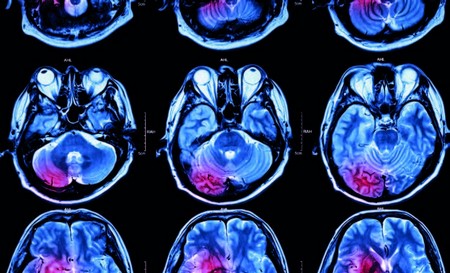

Cévní mozková příhoda je akutní stav, který vyžaduje neodkladnou lékařskou pomoc

foto: Profimedia